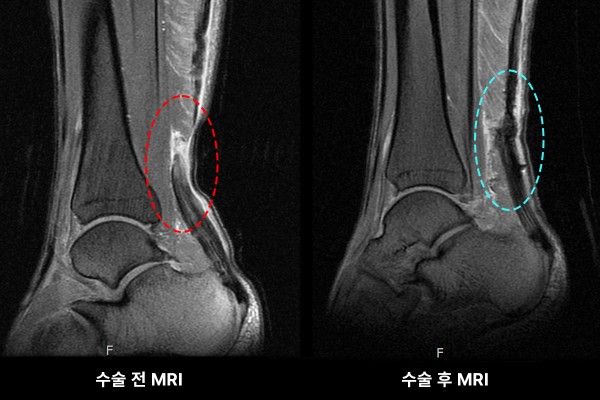

수술 전/후 MRI 사진을 보시면 파열되었던 아킬레스건이 잘 봉합(재건)되었음을 한 눈에 알 수 있습니다.